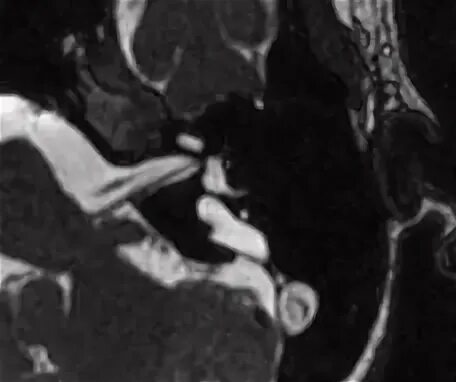

Мрт головного мозга мосто мозжечкового угла